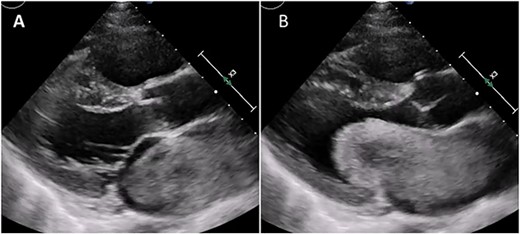

Median sternotomy was performed, and cardiopulmonary bypass was established via aortic and bicaval cannulation. Under cardiac arrest with antegrade cardioplegia perfusion, the LA was examined via the transseptal approach. The LA cavity was filled with the mass that the stalk was attached to the septal wall at the LA side, and the mass was too big and resected in pieces (Fig. 2). The mitral valve leaflet was intact, and the atrial septum was closed. Dilatated tricuspid annulus was fixed using a flexible band (Tailor Flexible band 29 mm, Abbott). After unclamping of the ascending aorta, a transesophageal echocardiogram points out moderate mitral regurgitation due to mitral annulus dilatation (Fig. 3). Cardiac arrest was performed again, and mitral annuloplasty was performed with a semi-rigid ring (Carpentier-Edwards Physio Ring II 26 mm, Edwards) via left atriotomy. His heart sinus rhythm returned to normal with successful weaning from cardiopulmonary bypass. After the transesophageal echocardiogram procedure, no evidence of the mass and residual mitral regurgitation was confirmed (Fig. 4).

Intraoperative transesophageal echocardiogram after the myxoma resection. Moderate mitral regurgitation with annulus dilatation was detected.